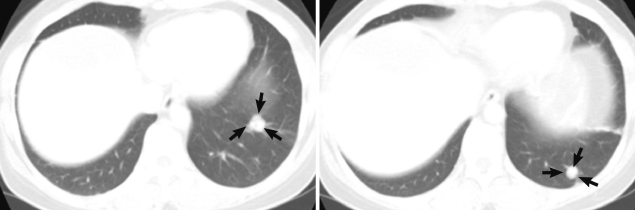

During follow-up, on 19 July 2005, a new nodular mass, 4.5×3.0 cm was observed in S5/8 segment of post-hepatectomized liver on CT imaging, and a needle biopsy of the mass showed coagulation necrosis. The hepatic mass was checked to be enlarged to 6.3×4.5 cm and several small nodules in both basal lungs on 7 August 2007. The hepatic mass showed extensive necrosis, and the pulmonary nodules represented calcification and focally impinged air, suggesting calcified granuloma rather than metastatic malignancy. On 7 May 2010, the hepatic mass was more enlarged, up to 10 cm in diameter and right supradiaphragmatic lymph node enlargement was found on contrast enhanced CT scan. Imaging study showed the same features of the previous mass (Fig. 1C, D). On the lung setting of chest CT scan, relatively well defined small nodules were seen in both lower lobes of the lung, suggestive for calcified granulomas, and metastasis, even less likely (Fig. 2). The eosinophilic count was 8.9% (reference value: 0-7%), total IgE was 1,944 kU/L (reference value: 0-200 kU/L), and parasitological studies were all negative for helminths, including Ascaris lumbricoides, Trichuris trichiura, Enterobius vermicularis, hookworms, and protozoa.

AE is rare but fatal. It has a risk of metastasis in advanced stages, usually resulting in secondary lesions in the lung or brain. A fatal outcome may occur in over 95% of untreated patients within a 10-year period following diagnosis [1]. When a slowly growing tumor, visualized by imaging techniques, is detected, a case is verified if at least 2 of the following 4 parameters are fulfilled, according to the WHO recommendations: 1) Typical organ lesions detected by imaging techniques, e.g., abdominal ultrasound, CT, and magnetic resonance imaging, 2) Detection of E. multilocularis specific serum antibodies by serotests, 3) Histopathology compatible with AE, 4) Detection of E. multilocularis nucleic acid in a clinical specimen [2,7]. CT imaging of slow growing and recurred mass in this case displayed ill-defined hypodense mass with poor or no enhancement after contrast injection and no differences on arterial and portal phase, which is characteristic for hepatic AE [8]. During the follow-up period of our case, multiple basal nodules at both lungs appeared, showing pulmonary extension. However, it is sometimes difficult to rule out other parasitic infections, pathologically and clinically, especially in non-endemic areas. Multiple cysts, mostly empty and histologically lamellated membrane along the inner side of the cysts with characteristic PAS (+) stain, are compatible with AE [2,4,8].

Fig. 2

Chest CT scan. Small nodules (arrows) are seen in the left lower lobe of the lung.

Fig. 2 Chest CT scan. Small nodules (arrows) are seen in the left lower lobe of the lung.